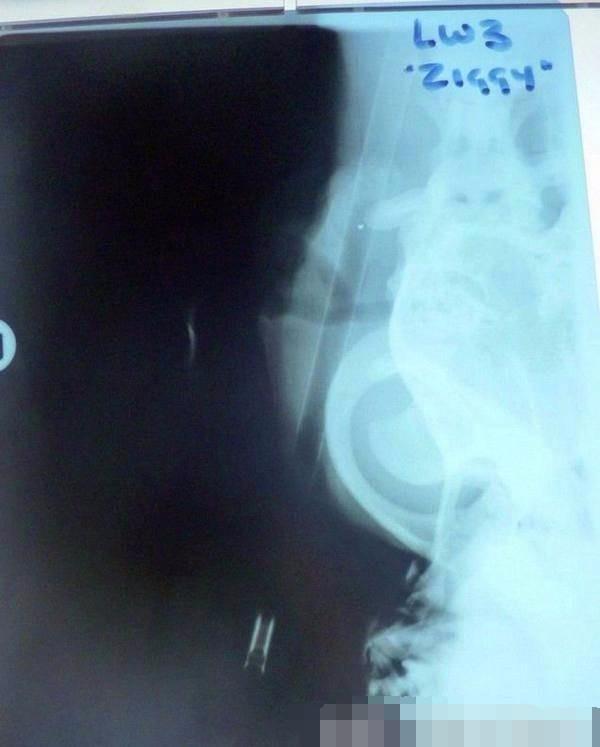

经过更为细致的检查后,医生发现弓箭长度约有70公分,而且是直接从狗狗的脑部穿插而过,所以当下就给狗狗实施了手术治疗,而狗狗强烈的求生意志也让它顺利的活下来了。